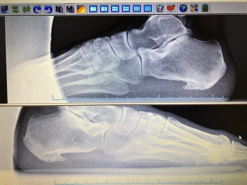

Artrosis en el tobillo:

Probablemente encontremos dolores localizados también en otras articulaciones. El cartílago es un tejido suave, elástico que protege las articulaciones y da movilidad a las mismas. Con el tiempo se desgasta y deja desprovisto de protección al hueso. No es reversible pero podemos detener su evolución.

Localizar el origen de comienzo de la lesión, como por ejemplo una mala pisada. Un estudio de la misma, junto con un buen tratamiento paliativo ortopodológico y un calzado específico puede reducir las molestias. En estos casos no se recomienda el uso de calzado muy blando y muy flexible.